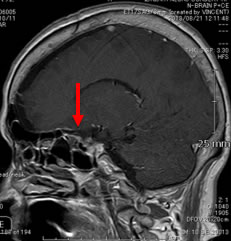

当院での症例をお示しします。症例は66才女性、進行する左眼の視力(左:手動弁)、視野障害にて当院来院。MRIにて赤矢印のように左蝶形骨内側に大きな腫瘍を認めます。開頭手術治療前に腫瘍の栄養血管にカテーテルを入れて、固体塞栓物質を造影剤と混ぜて注入します。最後に再開通しない様プラチナコイルを留置して終了します。その2日後に腫瘍摘出を行いましたが、出血は少量で輸血も行っておりません。視力も左は1.5まで改善し、患者さんは元気で退院しました。(図1-a・b、図2-a・b、図3-a・b、図4-a・b)

図2-b:術後矢印の腫瘍は消失 |

図2-b:術後 |